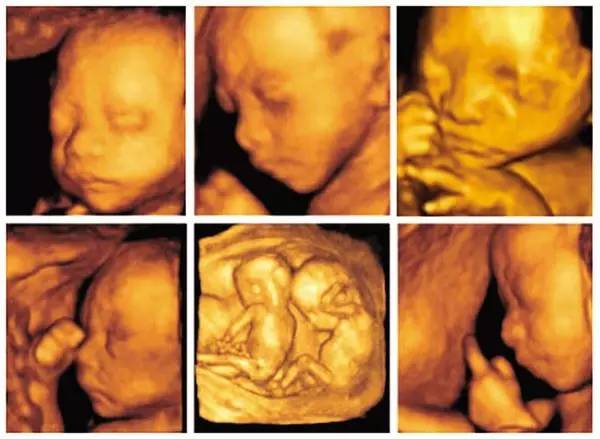

3D彩超,说就是平面的黑白B超再加上彩色多普勒,形成静态的三维图片,侧重观察五脏六腑是否畸形,排除结构畸形。

四维彩超,就是把不同时间的3D超声图像连成动图,实时的看到宝宝的动态活动,观察内容除了3D彩超内容外,还观察运动神经系统是否正常,运动是否协调。

二者选一种来做即可。

(图自网络)